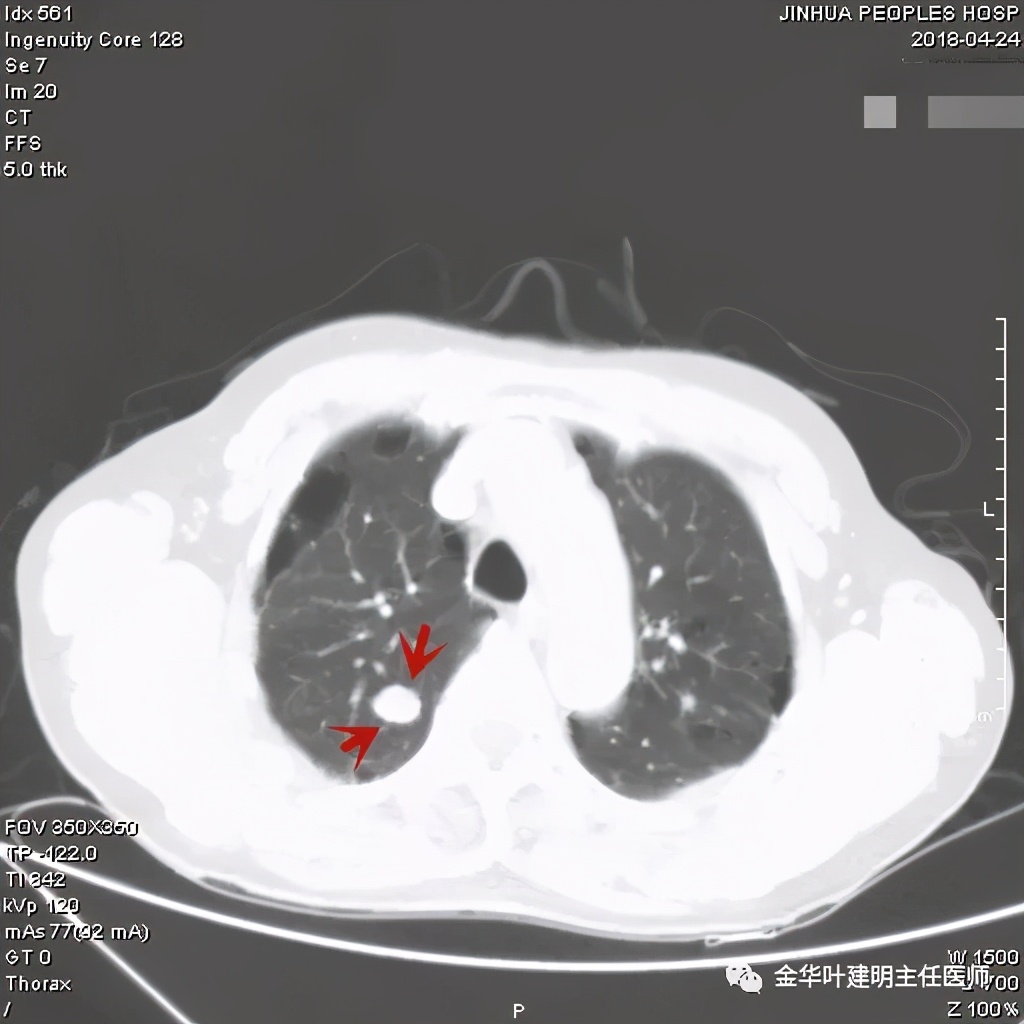

密度非常高的结节,边缘非常光滑

周围,边缘非常光滑,缺乏收缩力

高密度,周围,边缘非常光滑,亚厘米

高密度,边缘非常光滑,周围

这个也比较大,但边缘非常光滑,密度相对较为均匀

其实我们发现,包括今天这例,只要是错构瘤,“边缘非常光滑”是每一像都具备的!虽然有的似有支气管截断、有的似有血管征、有的似有分叶,但总的只要是边缘非常光滑的实性占位,就要想到错构瘤的可能,若有点状钙化密度,更是强烈要考虑。错构瘤如何靠近胸膜,其实可以切开一点肺实质,挤一下,肿瘤就会滚出来。